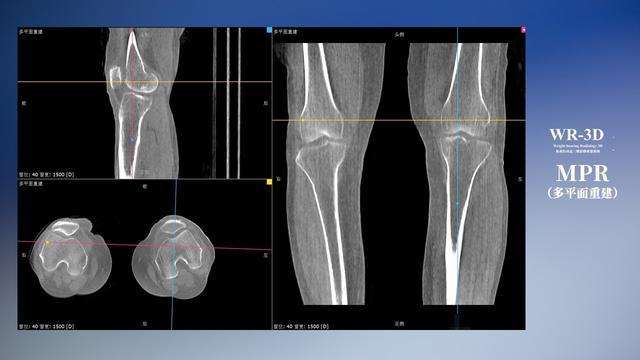

普通平片扫描与WR-3D扫描前后诊断结果对比

与此同时,数字化X线摄影技术相较于CTMRI来说,能快速获取真实、直观、满足临床需要的影像。DR的图像具有图像层次丰富、空间分辨力高、影像边缘锐利清晰、密度分辨力高级细微结构表现出色等特点,针对膝关节解剖结构数字化X线摄影技术应用价值很高,尤其是是对骨小梁与骨皮质的显示非常清楚。在负重位状态下,数字化X线三维摄影扫描与重建,能够更好的呈现受检者关节受力改变的状态。ty8天游平台登录科技创新的WR-3D动态三维数字化X线摄影技术,通过数字化X线摄影完成三维扫描并重建三维影像信息,包括MPR多平面重建、MIP重建以及VR绘制。扫描时间短,剂量相较于CT设备大幅缩减,同时成本更低,在临床诊断以及医疗方案制定中具有极大的价值意义。相较于普通平片下的负重位扫描,负重位动态三维扫描摄影技术能够避免二维状态下的组织结构重叠、密度分辨率不足、组织解剖结构难以分辨等问题,WR-3D支持多角度的动态三维摄影观察,能全面的呈现被检查部位在多个角度下三维影像信息,极大的减少了二维负重位检查的漏诊率。